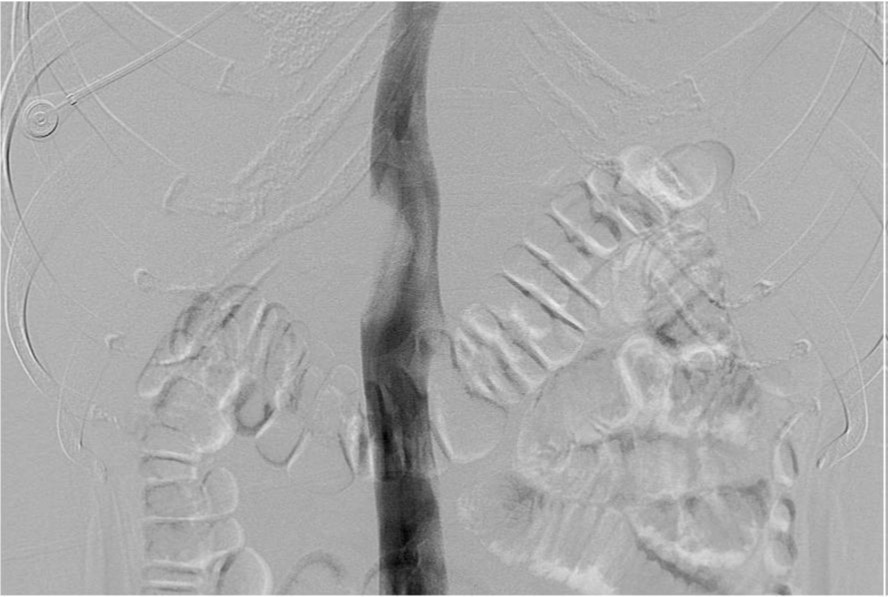

복부 컴퓨터단층촬영에서 12번 흉추골 높이의 하대 정맥에 2.5cm 크기의 공기방울을 포함한 혈전이 있다(Fig. 1A, IB). 하대정맥조영술에서 내경의 50%정도를 채우고 있는 혈전으로 인한 filling defect가 있다 (Fig. 2A). 혈전의 상부에 임시 하대정맥 필터로 Niti-S 스텐트를 삽입한 후 부분적으로(50%) 펼쳤다(Fig. 2B). Renal guiding catheter를 삽입하여 혈전에 대해 수차례 흡인 혈전제거술을 시행하여 다량의 백색혈전을 흡인하였다(Fig. 2C). 이후 시행한 하대정맥조영술에서 혈전의 일부가 스텐트 내부로 이동한 것을 확인하고 스텐트를 재포획하여 혈전을 제거하였다 (Fig. 2D). 스텐트에 혈전 및 나무재질의 이쑤시개가 배출되었다 (Fig. 3A, 3B).

Fig. 1. A

Fig. 1. Enhanced axial and coronal CT scan shows thrombus with air-bubbles in IVC adjacent to duodenal second portion.

Fig. 1. B